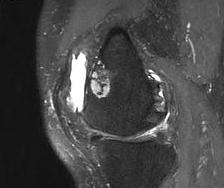

MRI

Can be very difficult to distinguish between low grade chondrosarcoma / atypical cartilaginous tumour and enchondroma

Low grade versus high grade chondrosarcoma

- MRI features associated with high grade versus low grade chondrosarcoma

- bone expansion / periostitis / soft tissue mass / tumour length